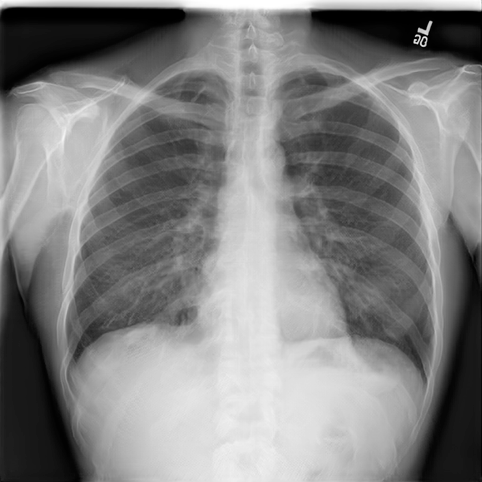

Experiment Setup

We used the NIH Chest X-ray 14 [73] dataset to conduct our experiments. This dataset consists of labeled chest X-ray images, from over unique patients corresponding to 14 common thoracic disease types, including atelectasis, cardiomegaly, effusion, infiltration, mass, nodule, pneumonia, pneumothorax, consolidation, edema, emphysema, fibrosis, pleural thickening, and hernia. The dataset is divided into training, validation, and testing sets, containing , . and images, respectively444We followed the dataset splits in https://github.com/zoogzog/chexnet/tree/master/dataset. Our experiments were designed to examine and compare four training methods:

Figure 7 samples real and GAN-generated images. The first column presents real images, the second column GAN-generated unsupervised, and the third GAN-generated supervised. The GAN-generated images may successfully fool our colleagues with no medical knowledge. However, as reported in [63], the GAN-generated labeled chest X-ray images must be screened by a team of radiologists to remove erroneous data (with respect to diagnosis knowledge). Without domain knowledge, incorrectly labeled images may be introduced by GANs into the training pool, which would degrade classification accuracy.

| Real | GAN unsupervised | GAN supervised |